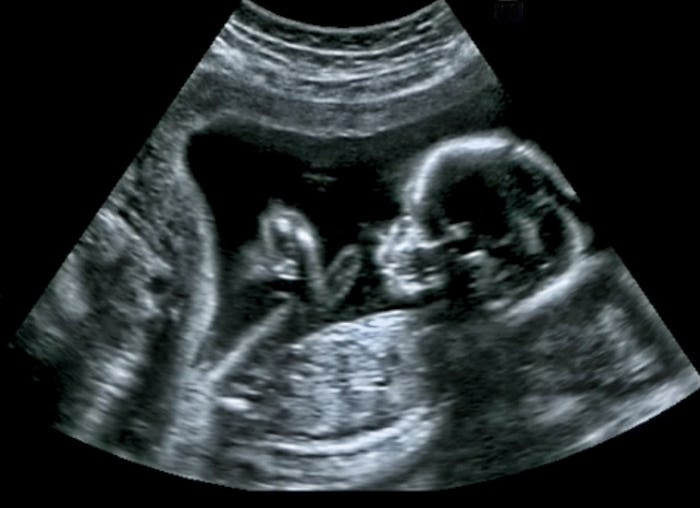

In order to understand when your baby can start kicking, you’ll need to know when your little one has the legs with which to accomplish the task. “Fetal limb buds are present at about six weeks gestation, and identifiable legs can be seen at about 9-10 weeks,” Dr. Kecia Gaither, MD, MPH, FACOG, double board-certified in OB/GYN and Maternal Fetal Medicine, Director of Perinatal Services at NYC Health + Hospitals/Lincoln, tells Romper. “Fetal movements can be seen at about eight weeks, and while kicking can be seen at about 9-10 weeks, movements are not felt by the mother generally until about 16-18 weeks.”

At some point, you might realize that you haven’t felt Baby moving for a while. Before you panic, make sure you stay calm. “If you have not felt 10 movements in the first hour, drink or eat a snack and count for another hour,” advises Dr. Demosthenes. “If you do not feel 10 movements in 2 hours, it is wise to call your maternity care provider.” An in-office ultrasound can make sure that your baby is safe and sound.